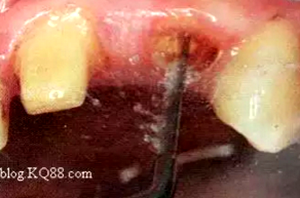

纖維樁修復(fù)之精細(xì)操作

(75%乙醇消毒根管)

(消毒后蒸餾水沖洗)

臨床建議使用75%乙醇消毒清潔根管后再用蒸餾水清洗。避免其他沖洗液相混合導(dǎo)致影響粘接強(qiáng)度。